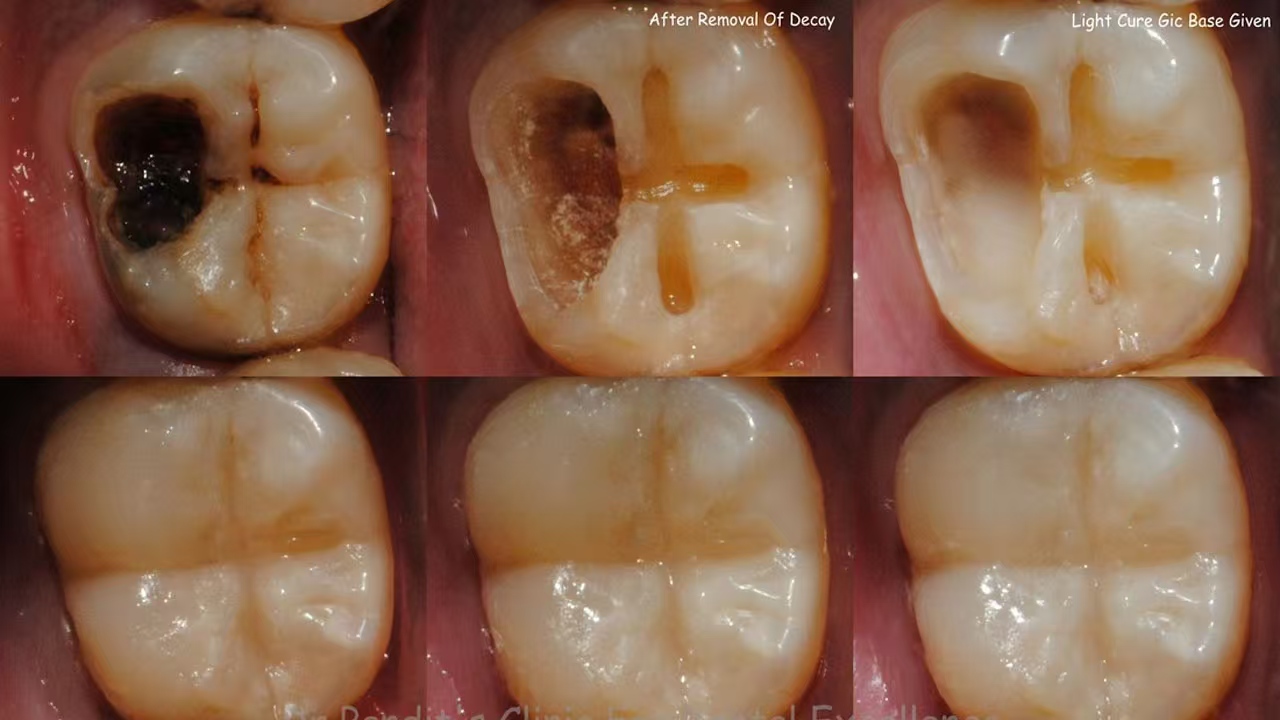

- Pit and Fissure Caries

Occurs in the grooves (fissures) and pits of posterior teeth (molars/premolars), where bacteria accumulate easily.

Clinical Relevance: Most common in children and adolescents due to deep occlusal surfaces.

- Acute Caries: Rapid progression, often painful, with soft, wet lesion texture.

- Chronic Caries: Slow progression, with hard, dry lesions and possible enamel remineralization if caught early.

- Structural Integrity: Fillings (e.g., composite resin, amalgam, ceramic) remove decayed tissue and restore tooth shape, enabling proper chewing and speech.